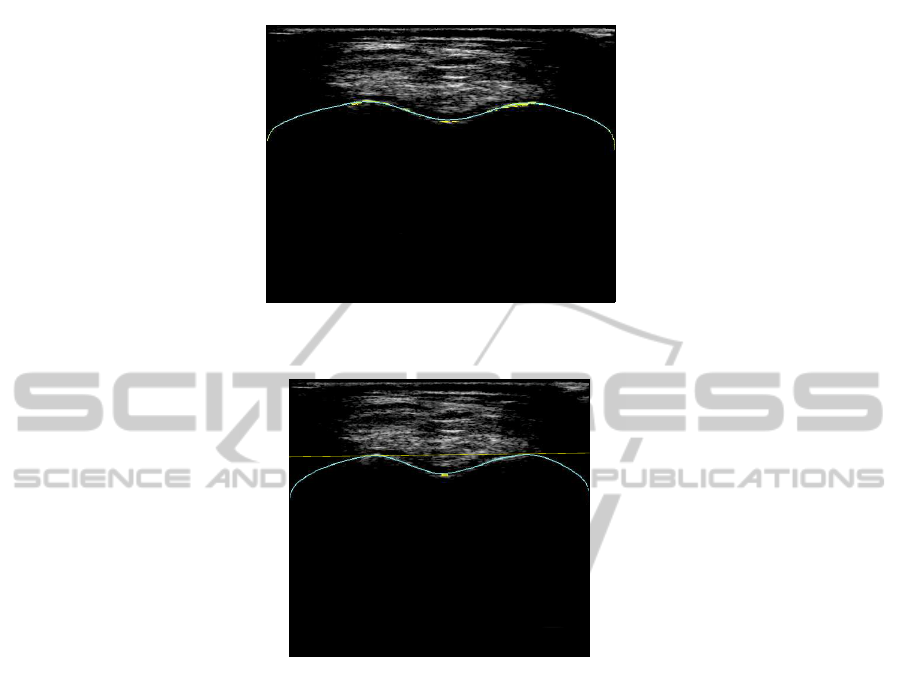

Fig.7.Some results of landmarks extraction. (a) Good detection of landmarks. (b) False detection.